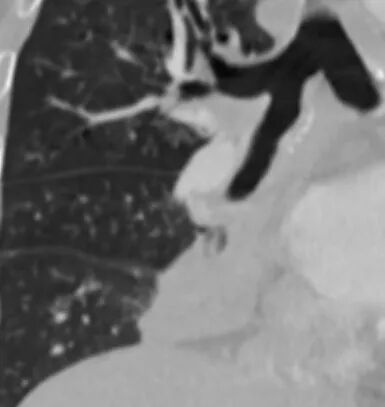

临床考虑肺结核,抗结核后3个月复查病灶明显缩小

琦遇:好病例!支气管爬行;右肺中叶有树芽征;右侧分支支气管壁弥漫性增厚了。右肺下叶内基底段支气管通而不畅。

两肺下叶背段都有病灶,可能大家忽略了。第二次复查的时候明显缩小,但是支气管还是没通,没敢除外肿瘤。第三次才全部吸收。这里放的是最后一次复查,已经完全吸收,中途还有一次复查部分吸收没放上来。

尘缘:患者炎性指标高,有支气管爬行征,支气管壁增厚,未完全堵塞,有点仙人掌的味道,而且纵隔脂肪间隙虽然模糊,但无明显肿瘤样强化。所以肯定先排查结核。所以用任何一种肿瘤都不好全部解释的,最先要排查的就是结核。